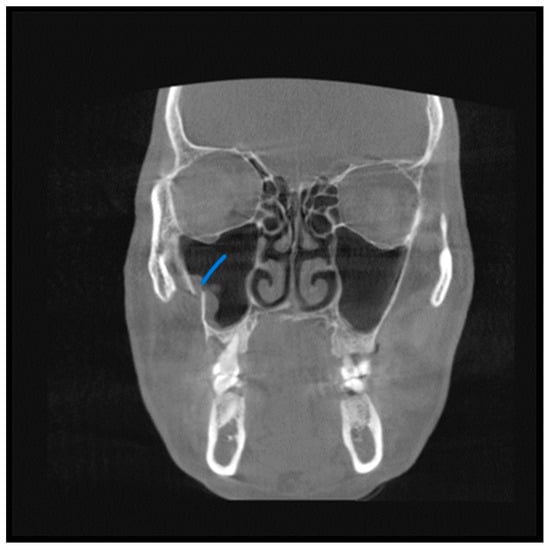

A total of 68 patients had pathologic findings in one or both sinuses, such as mucosal thickening, odontogenic cysts, fracture, hypoplasia, and bone lesions (58.1%) (Figure 1, Figure 2, Figure 3 and Figure 4). Of the 55 male patients, 33 had pathologies, like oroantral communication and inflammatory cysts in either sinus, whereas only 35 of the 62 scans of the female patients revealed radiographically abnormal findings in either sinus. The difference between the male and female patients was insignificant (Table 1).

Figure 2. View from the coronal plane. The Blue arrow shows a fracture line along the lateral wall of the maxillary sinuses.